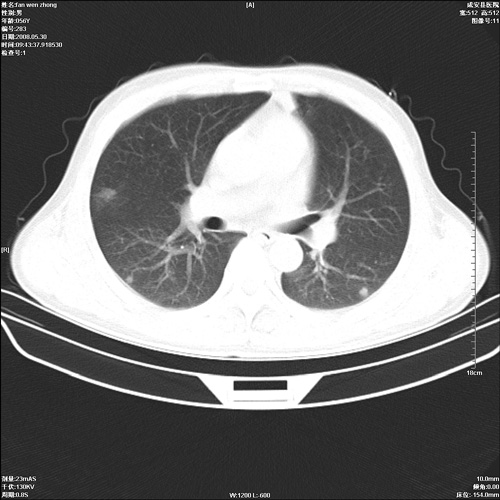

病人 男 56岁 一周前高热,体温达39-40度,经抗炎治疗后,体温渐降,达37,5-38度,轻微咳嗽,胸部不适 查白细胞为1.3万 行ct检查,请分析。

双肺内可见多发结节状病灶,并见小空洞,病人高热,白血球增高,应该是典型的迁徙性肺脓肿(多为金黄色葡萄球菌感染)。查一下口腔等其它部位有无感染灶。

双肺内可见多发结节状病灶,并见小空洞,病人高热,白血球增高,应该是典型的迁徙性肺脓肿(多为金黄色葡萄球菌感染)。建议治疗后复查.